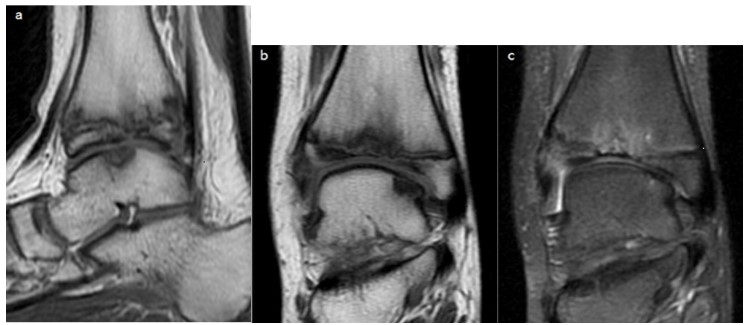

A 13-year-old boy was referred to the pediatric orthopedics department of our hospital with progressive pain in his right ankle over the past eight months. He did not recall any history of trauma to his ankle and had no medical history. He had no intensive sports training. On physical examination, he was overweight with a BMI of 27 Kg/m2. The right ankle was swollen, with normocoloured skin and without local heat. Its active and passive mobilization was painful with decreased mobility range. Neither foot deformity nor limb length discrepancy were noted. Blood tests were negative and an inflammatory or infectious etiology was ruled out. Antero-posterior radiographs of both ankles revealed a bilateral sclerotic and flattened median and lateral aspect of the distal tibial epiphyses predominantly on the right side (Figure 1).

Figure 1: Antero-posterior ankle radiographs of the right (a) and left (b) ankle showing bilateral flattening and sclerosis of the distal tibial epiphysis median and lateral aspect. Irregular narrowing of the distal physis is seen with sclerosis surrounding a lucency of the metaphyseal side of the growth plate.